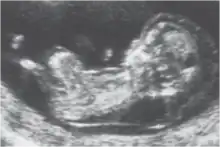

Clarté nucale

La clarté nucale, petite zone anéchogène (ne renvoyant pas d'écho en échographie) située sur le crâne d'un fœtus humain pendant le premier trimestre de grossesse, permet de dépister certaines anomalies congénitales, en particulier la trisomie 21.

La clarté nucale, comme son nom l’indique, se situe au niveau de la nuque du fœtus. Elle est due à un petit décollement entre la peau et le rachis et correspond à une zone dite anéchogène (c’est-à-dire qui ne renvoie pas d’écho lors de l’examen). Tous les fœtus présentent une clarté nucale au cours du premier trimestre, mais cette clarté disparaît ensuite.